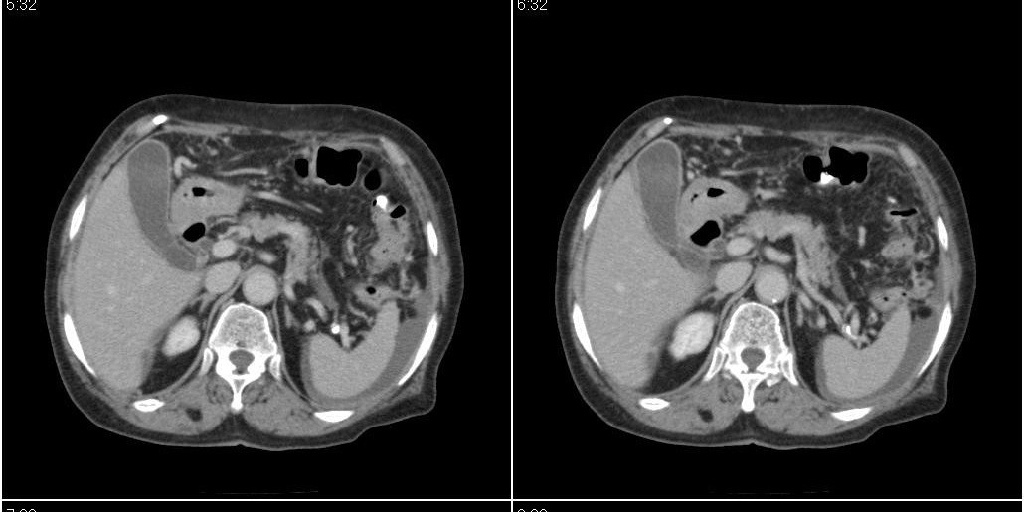

标题: CT24555:82岁女性,因为反复胸腹部积液进行CT检查,结果如下 [打印本页]

标题: CT24555:82岁女性,因为反复胸腹部积液进行CT检查,结果如下

胆囊有问题么,是结石么?胆囊内异常密度平扫30hu左右,增强各期无变化。

胆囊内稍高密度影,无强化,胆囊壁增厚,周围见低密度影,右侧膈肌角及脾周水样密度,支持胆囊泥沙样结石,胆囊炎、胆囊窝积液,胸腹水。